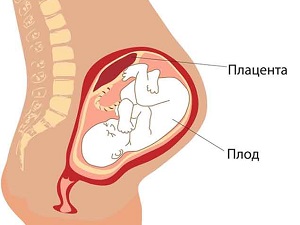

Плацента, або - має практично стерильне стан з постійною температурою всередині, щоб захистити зародок від хвороботворних бактерій і небезпечних інфекцій. На УЗД визначається ступінь зрілості плаценти, яка поступово потовщується і до 40 тижня досягає товщини в 3,5 см.

У плаценті 2 сторони: материнська, звернена до стінки матки, і дитяча (плодова), до якої кріпиться пуповина - через неї відбувається постачання дитини киснем і живильними речовинами.

При нормальному перебігу вагітності плацента розвивається найчастіше по задній стінці матки з переходом на бічні. Це викликано тим, що задня стінка матки менше схильна до фізіологічних змін і надійніше захищена від випадкового травматичного впливу.

Плацента має розташовуватися досить високо, не доходячи до внутрішнього краю шийки матки приблизно 6-8 см. У разі коли плацента внизу частково досягає зіву шийки матки або повністю його перекриває, діагностують передлежання - один з найсерйозніших видів акушерської патології. Точне уявлення про розташування плаценти можна отримати тільки після 32 тижня вагітності, оскільки локалізація плаценти змінюється в залежності від розміру і зміни форми матки.